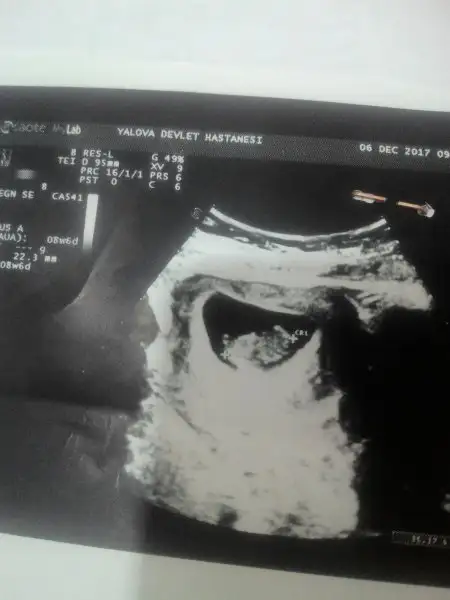

Bebeğin plasentası solda parlıyor ilk resimde. Kız derler ama. Dr ne dedi sana?evet canim bak atiyim tekrar 0Eki Görüntüle 2089138 asagidakide 8.6Eki Görüntüle 2089140